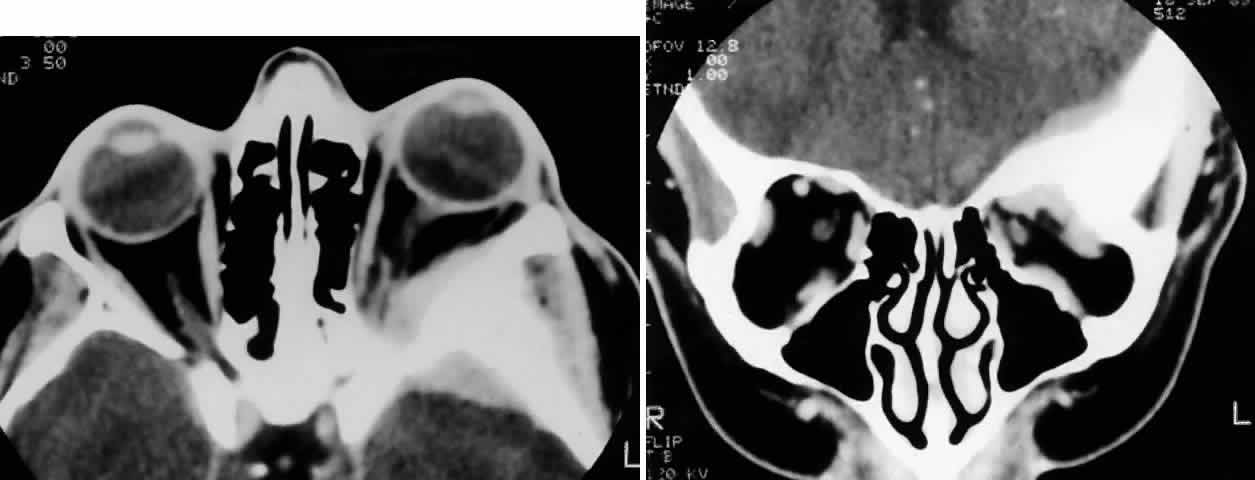

Radiologic findings consist of either focal or widespread destruction of the sinuses, with invasion of the adjacent structures by a solid tumor mass (Fig. 2). The mass is usually large; however, sometimes it may be relatively small but may extend to adjacent structures, particularly in the case of adenoid cystic carcinoma (Fig. 3). The sinus and orbit may be the only structures involved, but there is frequently extension to the base of the skull.

Fig. 2. A 32-year-old woman presented with a 1-month history of sinus congestion and nasal obstruction unresponsive to antibiotics. In the 1 week preceding the initial exam, the right eye became progressively more prominent and showed tearing and redness. On examination, there was mild edema of the lower lid and dysesthesia in the distribution of cranial nerve V2, and the globe was displaced 6 mm laterally and 5 mm anteriorly. There was mild limitation of abduction, chemosis, and nasal choroidal folds. An axial CT scan revealed a diffuse, destructive soft tissue mass centered in the superior nasal passage and ethmoid sinuses extending into the right orbit in contiguity with the medial rectus (A). On enhanced coronal view, the tumor was noted to involve the right maxillary antrum and to extend superiorly into the anterior cranial fossa (B). Biopsy of the sinus (C) revealed an alveolar-type rhabdomyosarcoma (muscle stain, × 320).